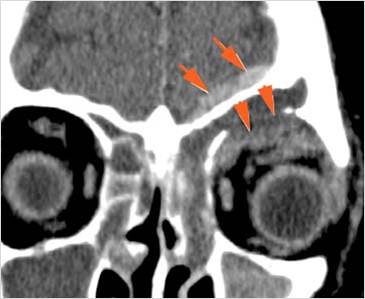

There is soft tissue swelling anterior to the frontal sinus or in the soft tissues surrounding the maxillary sinuses. [Yes/No]

There is a subperiosteal fluid collection or abscess along the boney walls of the anterior or middle cranial fossa. [Yes/No]

There is an epidural fluid collection or abscess along the boney walls of the anterior or middle cranial fossa. [Yes/No]